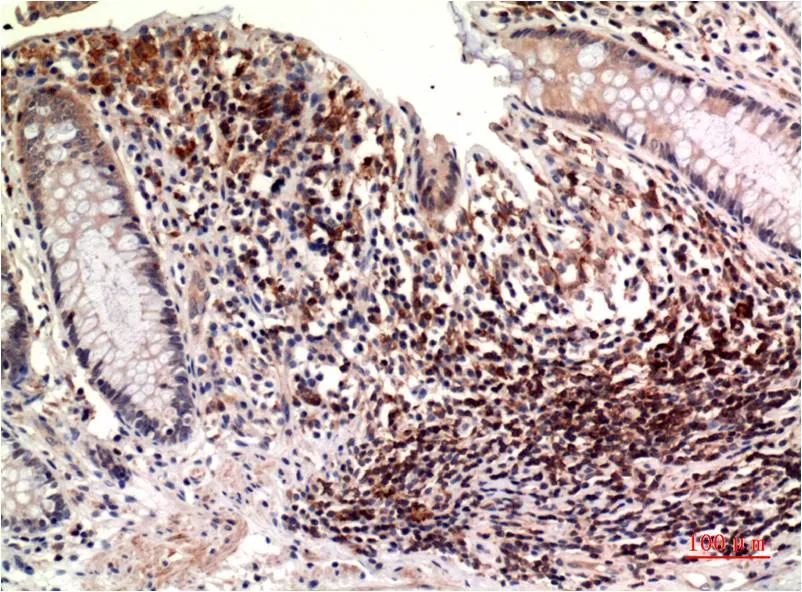

IL-8 (3A4) Mouse Monoclonal Antibody

Cat: AMM00739

Size1:50μL Price1:$150

Size2:100μL Price1:$280

Size3:500μL Price1:$280

Application:IHC-P

Reactivity:Human,Rat,Mouse

Conjugate:Unconjugated

Gene Name:CXCL8